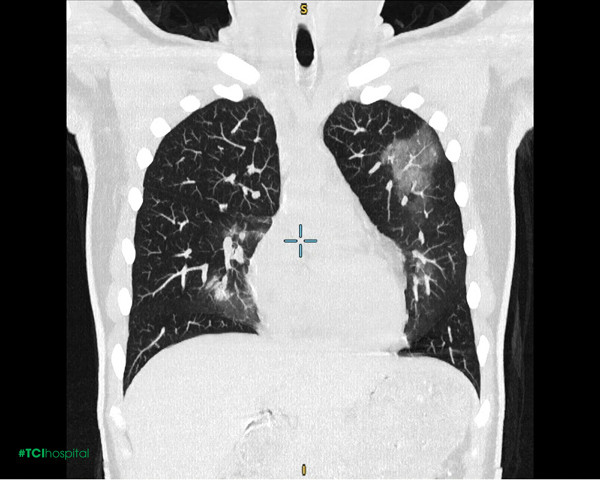

Chị N.T.T (35 tuổi) đến Hệ thống Y tế Thu Cúc TCI khám với biểu hiện ho khan, người mệt mỏi, tức vùng mũi sau 1 tháng mắc Covid-19. Bác sĩ Nội khoa tại TCI đã thăm khám và chỉ định chị T. chụp X-quang ngực thẳng. Kết quả trên phim chụp X-quang phát hiện có bất thường: Hình ảnh đám mờ không đồng nhất ngang mức cung trước xương sườn II-III bên trái. Kết hợp với ảnh chụp CT, chị T. được chẩn đoán viêm phổi đông đặc và xơ hóa phổi.

Được biết, chị N.T.T chỉ là một trong rất nhiều người bệnh đến Thu Cúc TCI thăm khám và phát hiện tổn thương tại phổi. Theo TS.BS CKI Nguyễn Đức Hoan - Giám đốc Phòng khám ĐK Thu Cúc 32 Đại Từ - Nguyên Phó Viện trưởng kiêm Chủ nhiệm Khoa Nội tổng hợp tại Viện điều trị cán bộ cao cấp Quân đội - Bệnh viên Trung ương Quân đội 108): “SARS-CoV-2 có áp lực mạnh mẽ với cơ quan hô hấp, gây tổn thương và để lại nhiều di chứng tại phổi. Các vấn đề về phổi thường gặp hậu Covid-19 gồm: viêm phổi, xẹp phổi, tràn dịch màng phổi, tràn khí màng phổi, áp xe phổi, đông đặc phổi, xơ phổi, tắc nghẽn mạch phổi,… Tổn thương phổi có thể xuất hiện ở cả trường hợp có bệnh lý nền hoặc không. Nếu không được điều trị kịp thời, các di chứng này sẽ gây suy giảm nghiêm trọng chức năng hô hấp và có thể đe dọa đến tính mạng người bệnh.”

Trong đó, chụp X-quang là chẩn đoán hình ảnh có thể phát hiện nhiều tổn thương ở phổi gồm: tổn thương tổ chức kẽ (hình ảnh lưới mờ, kính mờ, phù tổ chức kẽ); nốt mờ, bóng mờ khu trú hay lan tỏa; đông đặc nhu mô khu trú hay lan tỏa;... Kiểm tra lâm sàng và phim X-quang là căn cứ quan trọng để bác sĩ chỉ định sâu hơn nhằm phát hiện sớm các biến chứng nguy hiểm ở phổi như xơ phổi, tắc nghẽn mạch phổi,...